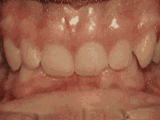

phase i

Patient's parents were concerned about both aesthetics and the health of the erupting permanent teeth when they brought him to the orthodontist at age eight. The lower front teeth were crowded and they touched the palate, and the upper front teeth were extremely displaced from their normal positions. After twenty months of Phase I treatment with an expander and partial braces, patient's appearance and dental function was vastly improved.